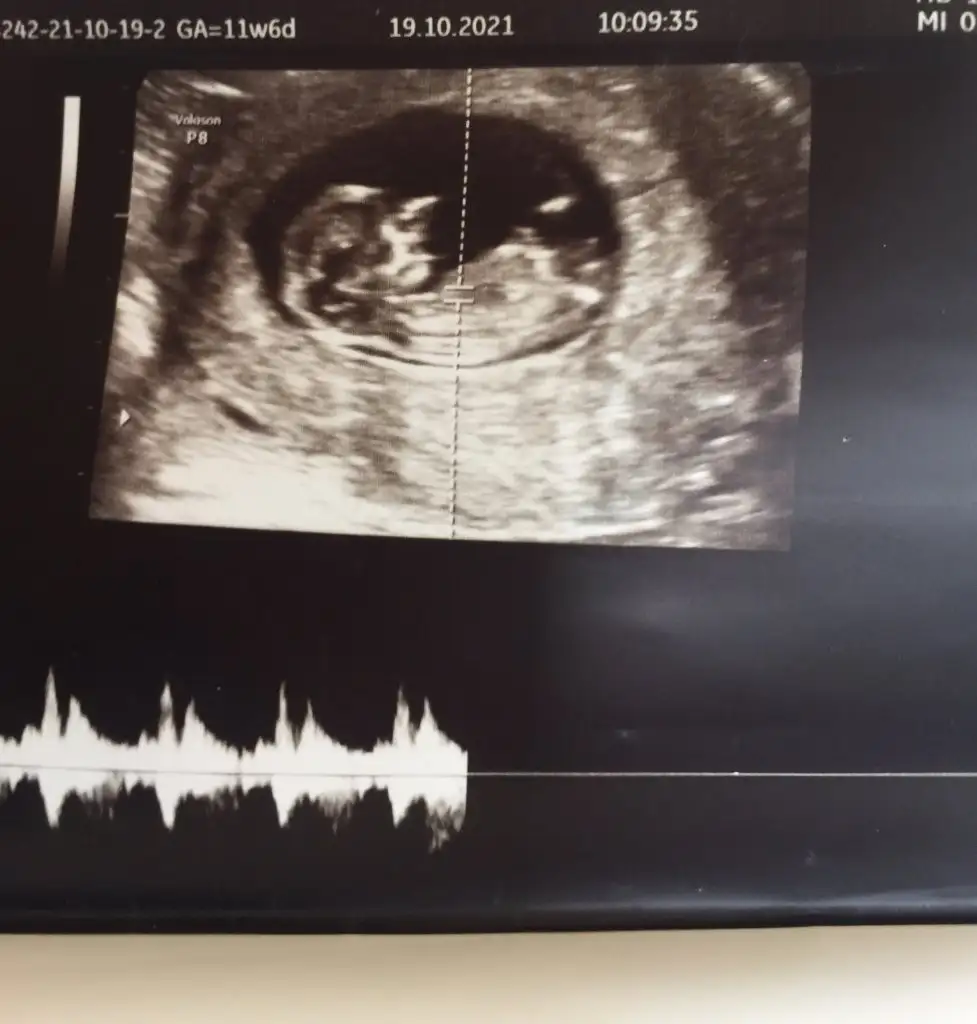

Emin olmadım sanki erkek gibiIkra meyra Merhaba, bu ultrason goruntuleri son adet tarihine gore 11+5, ultrason olcumune gore 12+3. Acaba cinsiyet icin bi yorum da bulunabilir misiniz ? Simdiden tesekkur ederim.

Emin olmadım başka USG varsa paylaşın sanki erkek gibi ama emin değilimIkra meyra rica etsem benim bebeğimi de tahmin eder misiniz 11+5

Eki Görüntüle 2936052

Eki Görüntüle 2936051